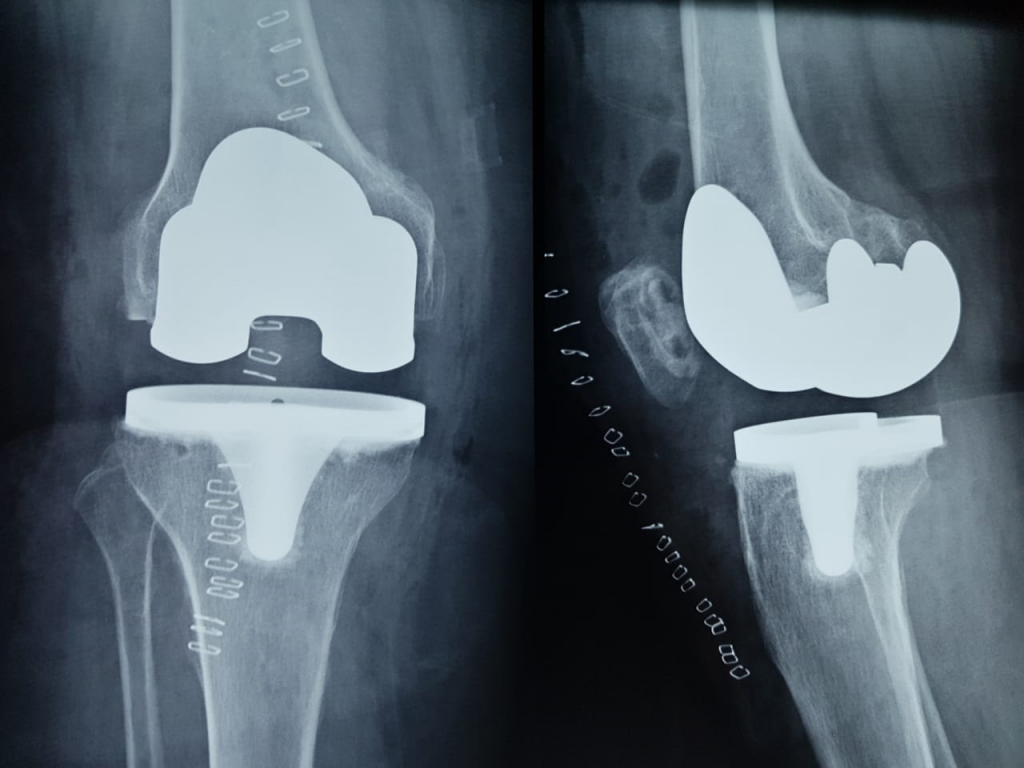

Remplazo Articular (protesis de rodilla y cadera)